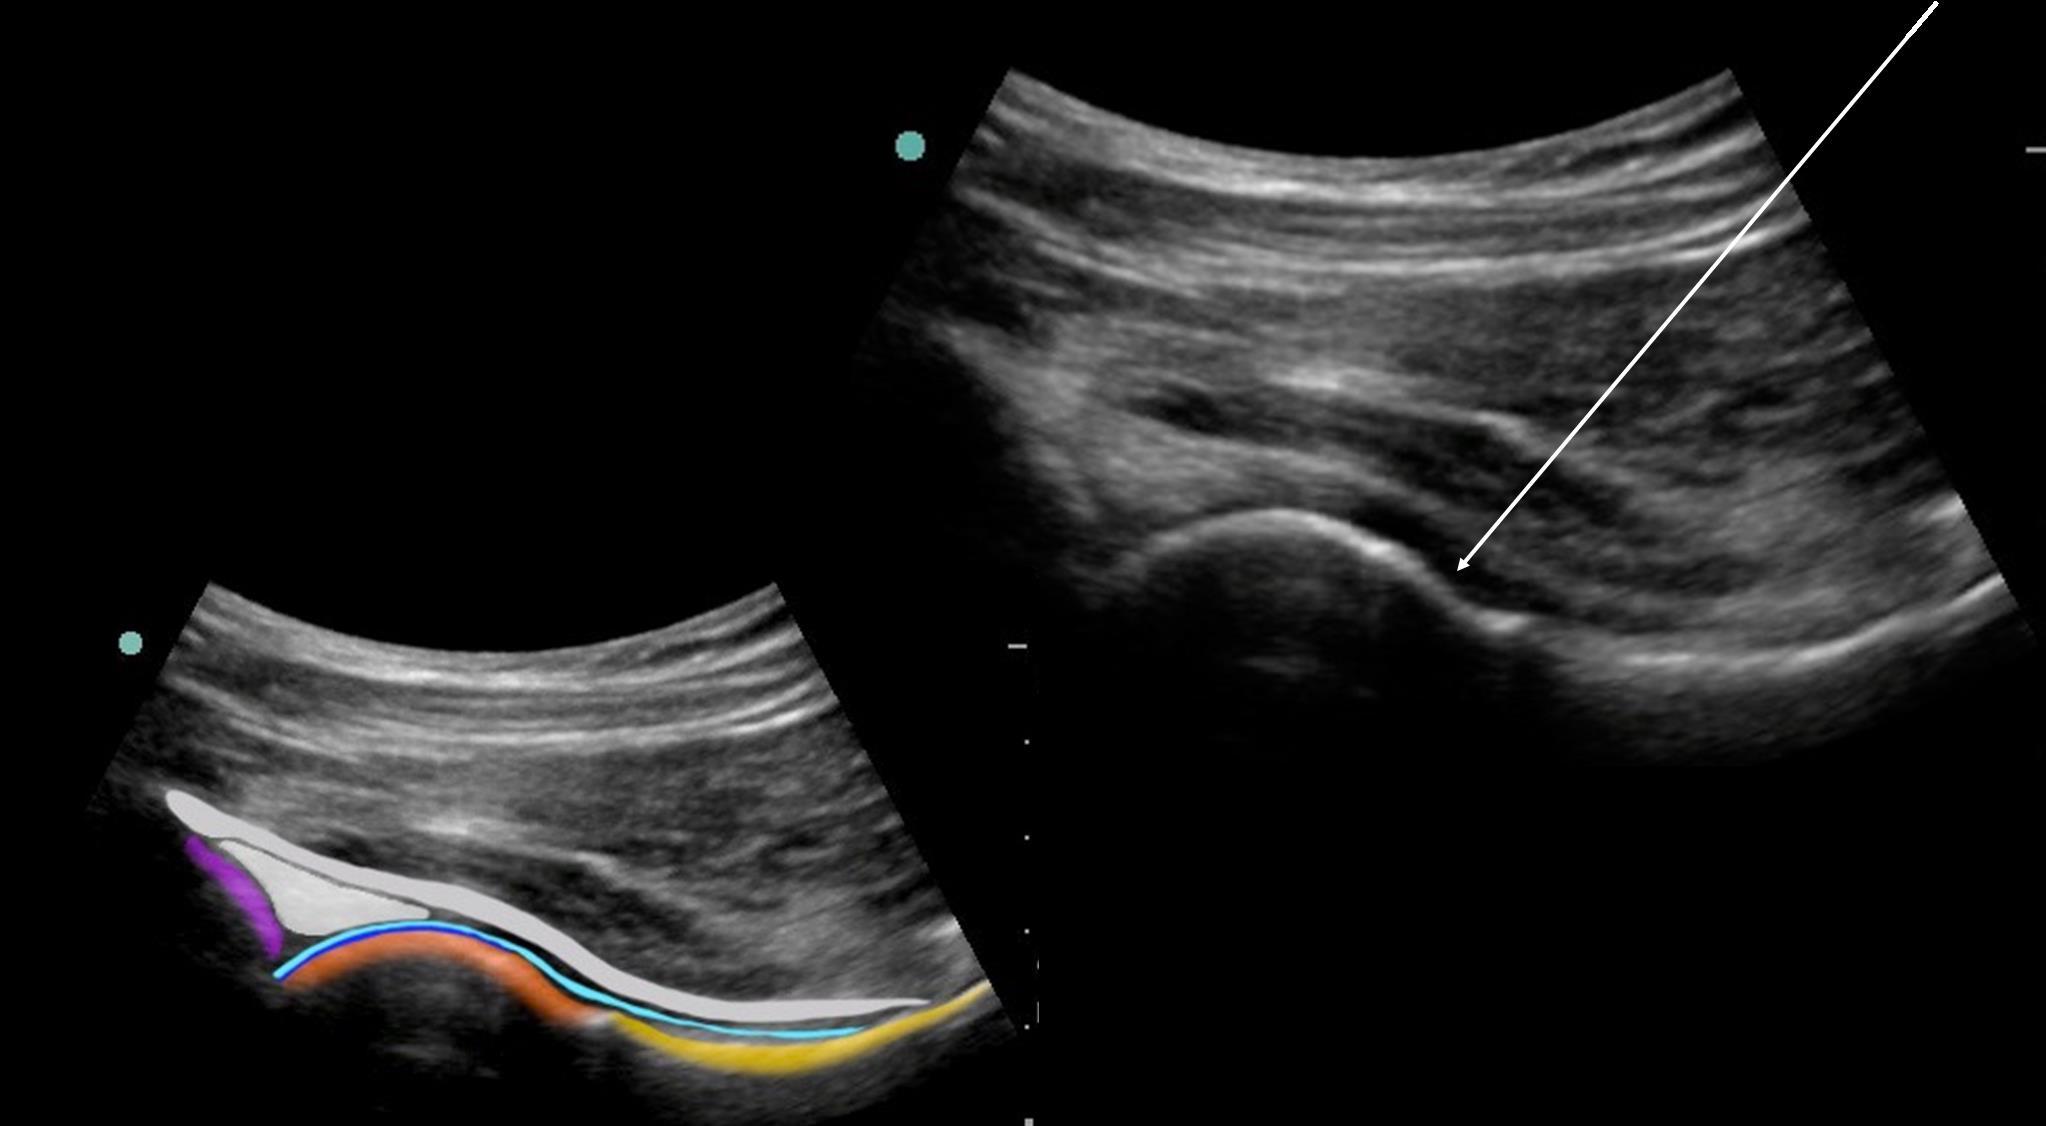

股関節注射針経路の画像